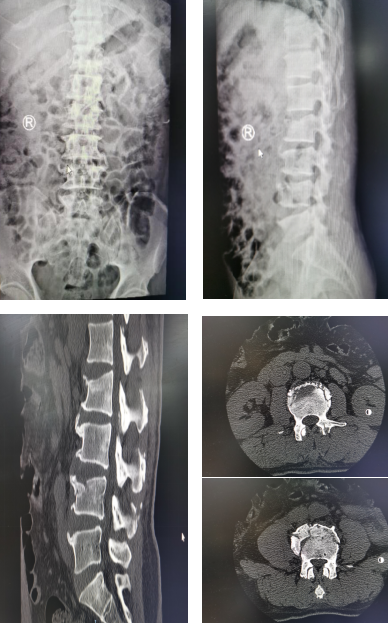

术前片

患者是一名55岁的男性,因高处坠落导致 L2、L4椎体骨折,疼痛,难以动弹。脊柱科孟磊副主任医师为患者检查后,和尚军主任进行了严谨的术前讨论,考虑到患者年纪不大,跨节段双椎体骨折,切开复位内固定术需剥离双侧椎旁肌,创伤大、出血多、术后疼痛恢复慢,因此,决定采取经皮椎弓根内固定术,可减少出血和对椎旁肌肉的干扰,有利于早期恢复并下地活动。